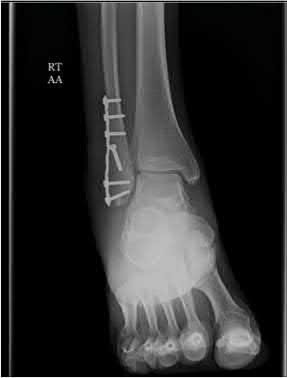

A 25-year-old male sustains an ankle fracture dislocation and undergoes open reduction and internal fixation. He returns to clinic five months following surgery complaining of continued ankle pain and instability with weight bearing. His immediate post-operative AP radiograph is seen in Figure A. Which of the following could have prevented this patient from developing persistent pain?

The patient presents with continued ankle pain and instability following open reduction and internal fixation. The radiograph in figure A demonstrates inadequate restoration of fibular length, likely leading to continued tibiotalar instability.

Illustration A demonstrates fibular malreduction with dislocation of the fibula anterior to the tibial incisura. Illustration B shows a comminuted fibula fracture along with a measurement of length from an intact fibula. The arc from the lateral process of the talus to the peroneal groove of the distal fibula is known as the "dime" sign and should remain unbroken if fibular length has been restored. Illustration C demonstrates the use of a push-pull screw and lamina spreader to regain length intraoperatively for a comminuted fibula fracture.

Chu and Weiner review management of malunions of the distal fibula. The authors state that restoration of fibular length, alignment and rotation leads to reduction of the talus, provides a buttress to talar motion in the setting of an incompetent deltoid, and allows the syndesmotic ligaments to heal at the appropriate tension.

Wikeroy et al conducted a study of patients from a prior prospective, randomized control trial comparing different methods of syndesmotic fixation. There was no significant difference in outcomes between tricortical or quadricortical 3.5mm screw fixation, however worse outcomes were seen with associated posterior malleolar fractures, obesity, a difference in sydesmotic width of 1.5mm or greater, and a CT confirmed tibio-fibular synostosis.

Sinha et al present a simple technique for fibular lengthening in the setting of distal fibula malunion. They found high union rates and improved AOFAS scores at short-term follow up with their technique.